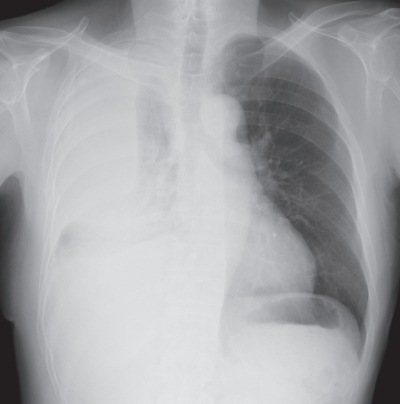

体温36.3 ℃。脈拍 72/分、整。血圧 128/72 mmHg。呼吸数 18/分。SpO₂ 98 %(room air)。右胸部の呼吸音は減弱し、打診で濁音を認める。血液検査所見で炎症所見は認めないが、胸水中のヒアルロン酸は 125,000 ng/mL と著明な増加を認めた。胸部エックス線写真と胸部造影 CTを別に示す。